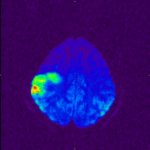

MR-Angiographie (MRA) meiner Halsgefäße |

Zwei Arterienpaare übernehmen die Blutzufuhr zum Gehirn (Arteria

carotis interna) und (Arteria vertebralis).

Beide vereinigen sich in der Hirnbasis zu einem

ringförmigen Arterienkreis, dem Circulus Willisii. Vom

Willisi-Kreis gehen paarweise die drei großen Hirnarterien ab,

die vordere, mittlere und hintere Hirnarterie. |

MR-Angiographie (MRA) meiner

Hirnbasisarterien

(Circulus Willisi) |

gut sichtbar distale Stenose Arteria

carotis rechts |